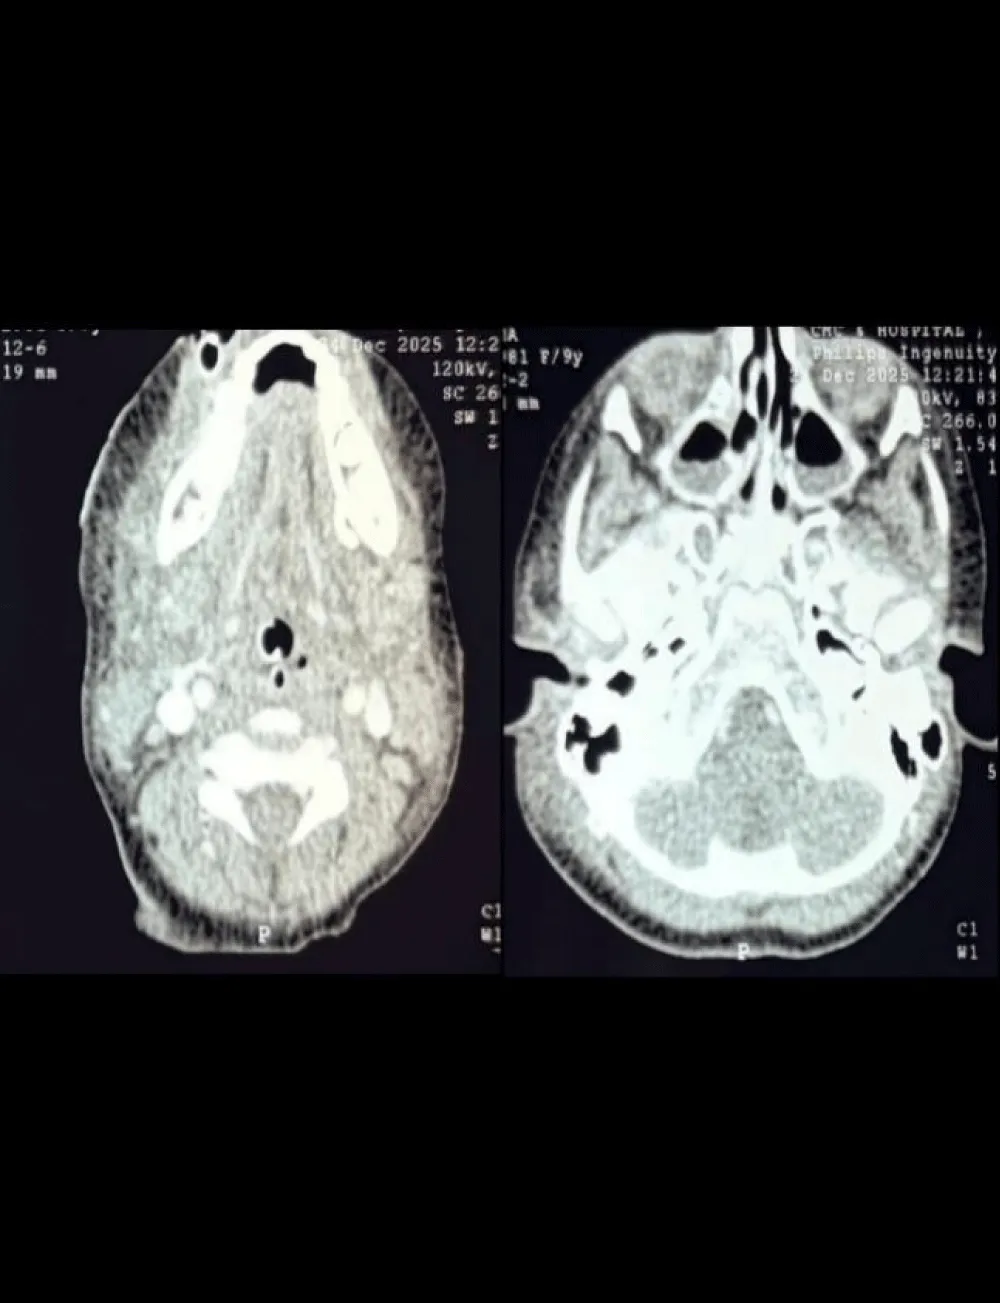

CT scanning is highly effective in evaluating deep neck spaces and mediastinal abscesses. Although MRI provides superior soft tissue resolution, its longer acquisition time limits its utility in acute settings; CT is the imaging modality of choice [7,11]. In our case, the patient had no comorbidities, and her recovery from the illness was hastened after the surgical decompression and broad-spectrum intravenous antibiotics. Contrast CT imaging of the neck was done, which illustrated ill-defined collections involving the floor of the mouth, right parotid space, bilateral submandibular space, right masticator space, anterior cervical space on the left side, and right parapharyngeal space. Inferiorly extending to the visceral space of the neck at the T1/T2 intervertebral disc level (Figures 2,3).